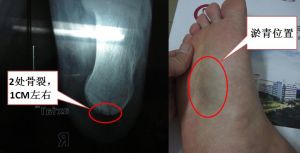

凡疑為骨折者應常規進行X線拍片檢查,可以幫助了解骨折的類型和具體情況,對治療具有指導意義。骨折的X線檢查一般應拍攝包括鄰近一個關節在內的正、側位片,必要時須加攝斜位、切線位或健側相應部位的X線片。裂紋在沒有明顯移位時常看不見,必要時行CT和磁共振(MRI)進一步明確診斷,MRI可根據組織在磁場中的信號強度變化來顯示包括骨水腫在內的病變。